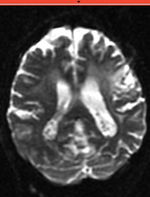

baseline & T2 before registration baseline to T2 after affine+nonrigid alignment DTI and T2 before & after registration

• the strong EPI-based distortions of the DTI image make nonrigid registration necessary

• initial alignment & overlap is sufficient so that no "initialization" methods are necessary and registration can succeed without.